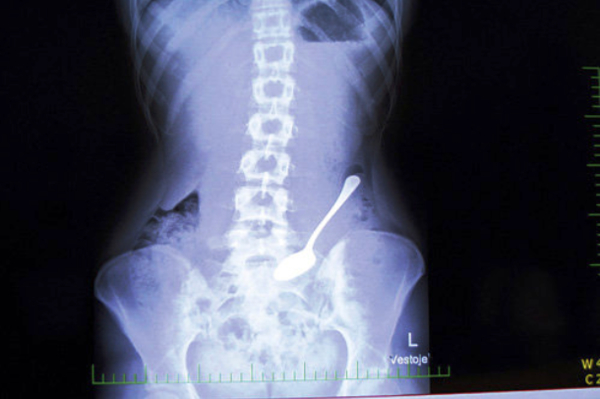

Неожиданные находки в теле человека: ТОП-20 фото

Люди порой поражают медиков странными вкусовыми пристрастиями и удивляют неожиданными вещами, которые по разным причинам оказались в человеческом теле и доступны взору только на рентгеновских снимках. Смотри подборку самых неожиданных находок в человеческом организме

Некоторые люди умудрились удивить медиков странными находками, обнаружившимися в их желудках и телах на рентгеновских снимках. Следует отметить, что многие предметы оказались в человеческом организме волей случая, но некоторые из них - по воле их носителей.